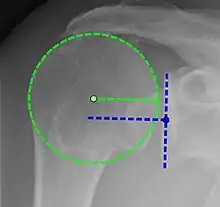

Xray

X-ray projectional radiography cannot directly reveal tears of the rotator cuff, a 'soft tissue', and consequently, normal X-rays cannot exclude a damaged cuff. However, indirect evidence of pathology may be seen in instances where one or more of the tendons has undergone degenerative calcification (calcific tendinitis). The humeral head may migrate upward (high-riding humeral head) secondary to tears of the infraspinatus, or combined tears of the supraspinatus and infraspinatus.[51] The migration can be measured by the distance between:

- A line crossing the center of a line between the superior and inferior rims of the glenoid articular surface (blue in image).

- The center of a "best-fit" circle positioned over the humeral articular surface (green in image)

Normally, the former is positioned inferiorly to the latter, and a reversal therefore indicates a rotator cuff tear.[51] Prolonged contact between a high-riding humeral head and the acromion above it may lead to X-ray findings of wear on the humeral head and acromion; secondary degenerative arthritis of the glenohumeral joint (the ball and socket joint of the shoulder), called cuff arthropathy, may follow.[50] Incidental X-ray findings of bone spurs at the adjacent acromioclavicular joint may show a bone spur growing from the outer edge of the clavicle downward toward the rotator cuff. Spurs may also be seen on the underside of the acromion, once thought to cause direct fraying of the rotator cuff from contact friction, a concept currently regarded as controversial.